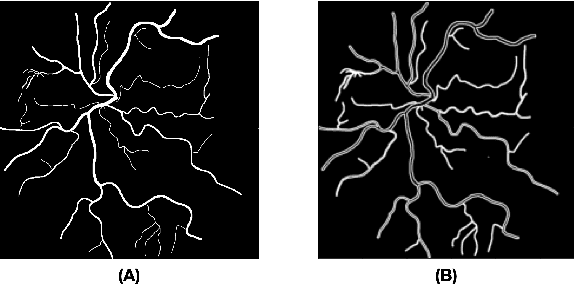

Abstract:The retina is the only part of the human body in which blood vessels can be accessed non-invasively using imaging techniques such as digital fundus images (DFI). The spatial distribution of the retinal microvasculature may change with cardiovascular diseases and thus the eyes may be regarded as a window to our hearts. Computerized segmentation of the retinal arterioles and venules (A/V) is essential for automated microvasculature analysis. Using active learning, we created a new DFI dataset containing 240 crowd-sourced manual A/V segmentations performed by fifteen medical students and reviewed by an ophthalmologist, and developed LUNet, a novel deep learning architecture for high resolution A/V segmentation. LUNet architecture includes a double dilated convolutional block that aims to enhance the receptive field of the model and reduce its parameter count. Furthermore, LUNet has a long tail that operates at high resolution to refine the segmentation. The custom loss function emphasizes the continuity of the blood vessels. LUNet is shown to significantly outperform two state-of-the-art segmentation algorithms on the local test set as well as on four external test sets simulating distribution shifts across ethnicity, comorbidities, and annotators. We make the newly created dataset open access (upon publication).